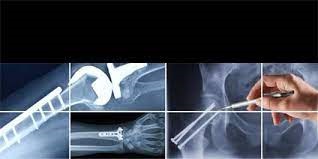

محققان گروه جراحی ارتوپدی دانشگاه علوم پزشکی مشهد موفق به طراحی و ساخت پلاک استخوانی تغییر زاویه و پلاک استخوانی کوتاه کننده و بلند کننده و ثبت اختراع آن شدند. عضو هیأت علمی دانشگاه علوم پزشکی مشهد و مخترع این دو دستگاه در گفتگو با وب دا اظهار کرد: در عمل های جراحی ارتوپدی به خصوص در سالمندان، نیاز به ابزار کمک کننده ای است که بعد از عمل بتوان شرایط دوران نقاهت را برای بیماران تسهیل کرد. دکتر امید شاهپری در تشریح ساخت پلاک استخوانی کوتاه کننده و بلند کننده خاطر نشان کرد: در مواردی که نیاز به کوتاه کردن استخوان باشد یک قطعه استخوان به طول مناسب برداشته می شود و دو انتها مجدد روبروی هم قرارداده شده و با پلاک ثابت می شود تا طول مناسب بدست بیاید همچنین جهت افزایش طول استخوان پس از استئوتومی یک قطعه گرافت استخوانی با اندازه مناسب در بین محل استئوتومی گذاشته می شود و با پلاک ثابت می شود. وی تصریح کرد: پلاک استخوانی تغییر زاویه نیز در بیمارانی که دچار آرتروز شده اند و یا به هر علتی عضو از مسیر اصلی منحرف شده است ، کاربرد درمانی دارد. وی با بیان اینکه بیماریهای گروه ارتوپدی در تمام مقاطع سنی مشهود است، ابراز کرد: اما سالمندان از آن دسته افرادی هستند که در اعمال جراحی باید تلاش شود بهبودی بهتری نصیب بیمار شود. |